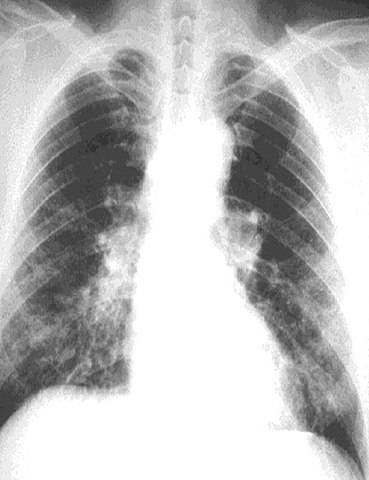

radiografía dun pulmón con asbestose

Steve M. Radiografía dun pulmón con asbestose (CC BY-SA)

Por exposición a riscos ambientais ou laborais

Comprenden un amplo grupo de enfermidades que dependen dos riscos aos que están expostos.  Exemplos: Asbestose por amianto ou bursite por carga de pesos excesivos.

11. Por Exposición a Riscos Ambientais ou Laborais

Dependen dos riscos aos que se está exposto.

Exemplos: Asbestose por amianto, bursite por cargar pesos excesivos